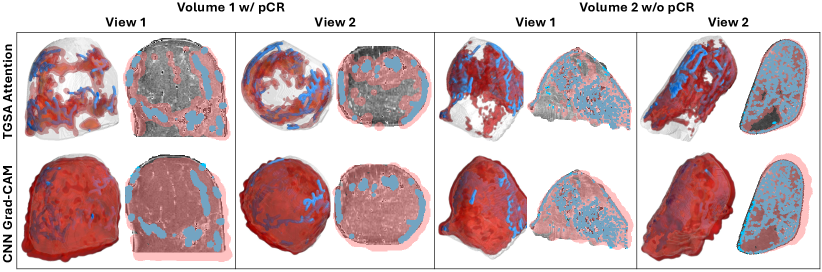

The key idea in TopoTxR lies in its ability to direct CNN’s attention to a much smaller set of voxels with high biological relevance manifested by the extracted topological structures. As shown in Sec. 3, these structures have a strong connection with the breast tissue. In this section, we prove that voxels corresponding to topological structures play an essential role when CNN is making a pCR prediction. We visualize the spatial attention using a post-hoc heatmap visualization technique – Gradient-weighted Class Activation Mapping (Grad-CAM) [62]. Grad-CAM generalizes Class Activation Mapping (CAM) [85] by lifting its constraints on model complexity and provides good visual explanations for model decisions. It generates a coarse localization map that highlights key regions in the imaging data pivotal for predicting a specific concept. Our aim is to utilize Grad-CAM to gain interpretative insights into the decision-making process of TopoTxR. It is important to note that Grad-CAM does not alter the learning mechanism of the model. It is applied post-training to a model with fixed weights, serving purely as a tool to shed light on how the model arrives at its decisions.

We employ the Grad-CAM implementation from the M3d-CAM library [22] to visualize attention maps following the Topology-Guided Spatial Attention (TGSA) module in the best-performing TopoTxR model. For comparison, we modify the TopoTxR model to exclude the TGSA module, utilizing a single 3D CNN branch that processes only raw MRI data. In this setup, Grad-CAM is applied after the third convolution layer to visualize attention maps, as depicted in the second row—’CNN Grad-CAM’ in Fig. 8. Conversely, the attention maps from our proposed model are shown in the first row—’TGSA Attention.’ In Fig. 8, we provide a comparative analysis of the attention maps from two views, showcasing one representative sample each for cases with and without pCR. This comparison highlights that the TGSA module effectively directs the CNN’s focus to specific, biologically relevant regions, as delineated by topological structures. Conversely, the model lacking topology information shows a more scattered and dispersed attention distribution across the MRI volume. It is interesting to note that the topological structures appear sparser in cases with a pCR, whereas they are denser in cases without pCR.